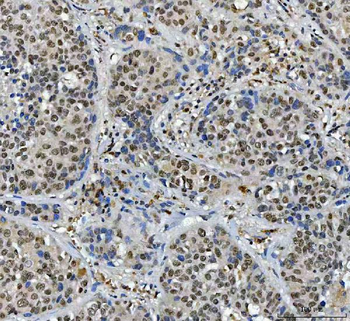

Antibody used in IHC on Human Skin at 4.0-8.0 ug/ml.